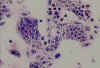

Figure 3 b:

Cells stained with Giemsa.